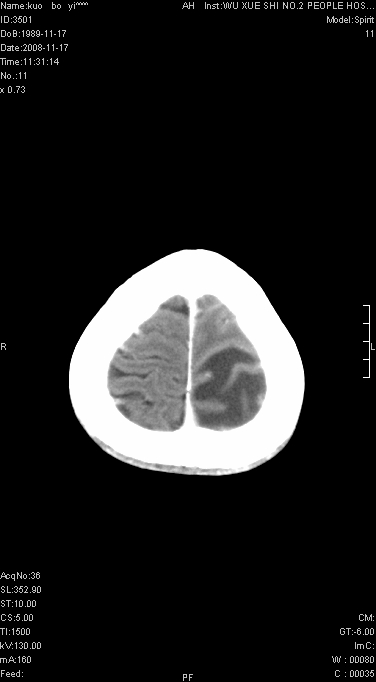

考虑左侧顶叶脑炎可能;建议追踪复查。

左顶叶较大范围水肿区,内见明显强化的片状 棉絮状组织,但占位效应不明显。多考虑:脑炎!

还是考虑原发脑胶质瘤,梗塞缺血水肿的低密度要同时累及皮、髓质并要符合动脉供血的区域分界特点,本例强化后见瘤体结节及向周围浸润生长的瘤血管都强化了,水肿广泛呈指状,占位效应使同侧脑皮质受压变薄、脑沟消失但因实质性的瘤体尚小所以中线无明显移位。不知各位同意这样分析吗?(转移瘤多为多处病灶)

左顶叶大范围水肿,内见明显强化的片状 棉絮状组织,但占位效应不明显。考虑脑炎可能性大。

在北京天坛医院治疗考虑寄生虫感.明显好转